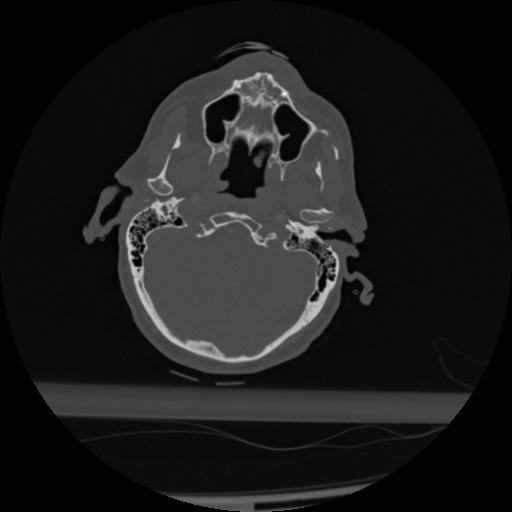

22 ANGIO,CE,Vol,0.5,ANGIO,,